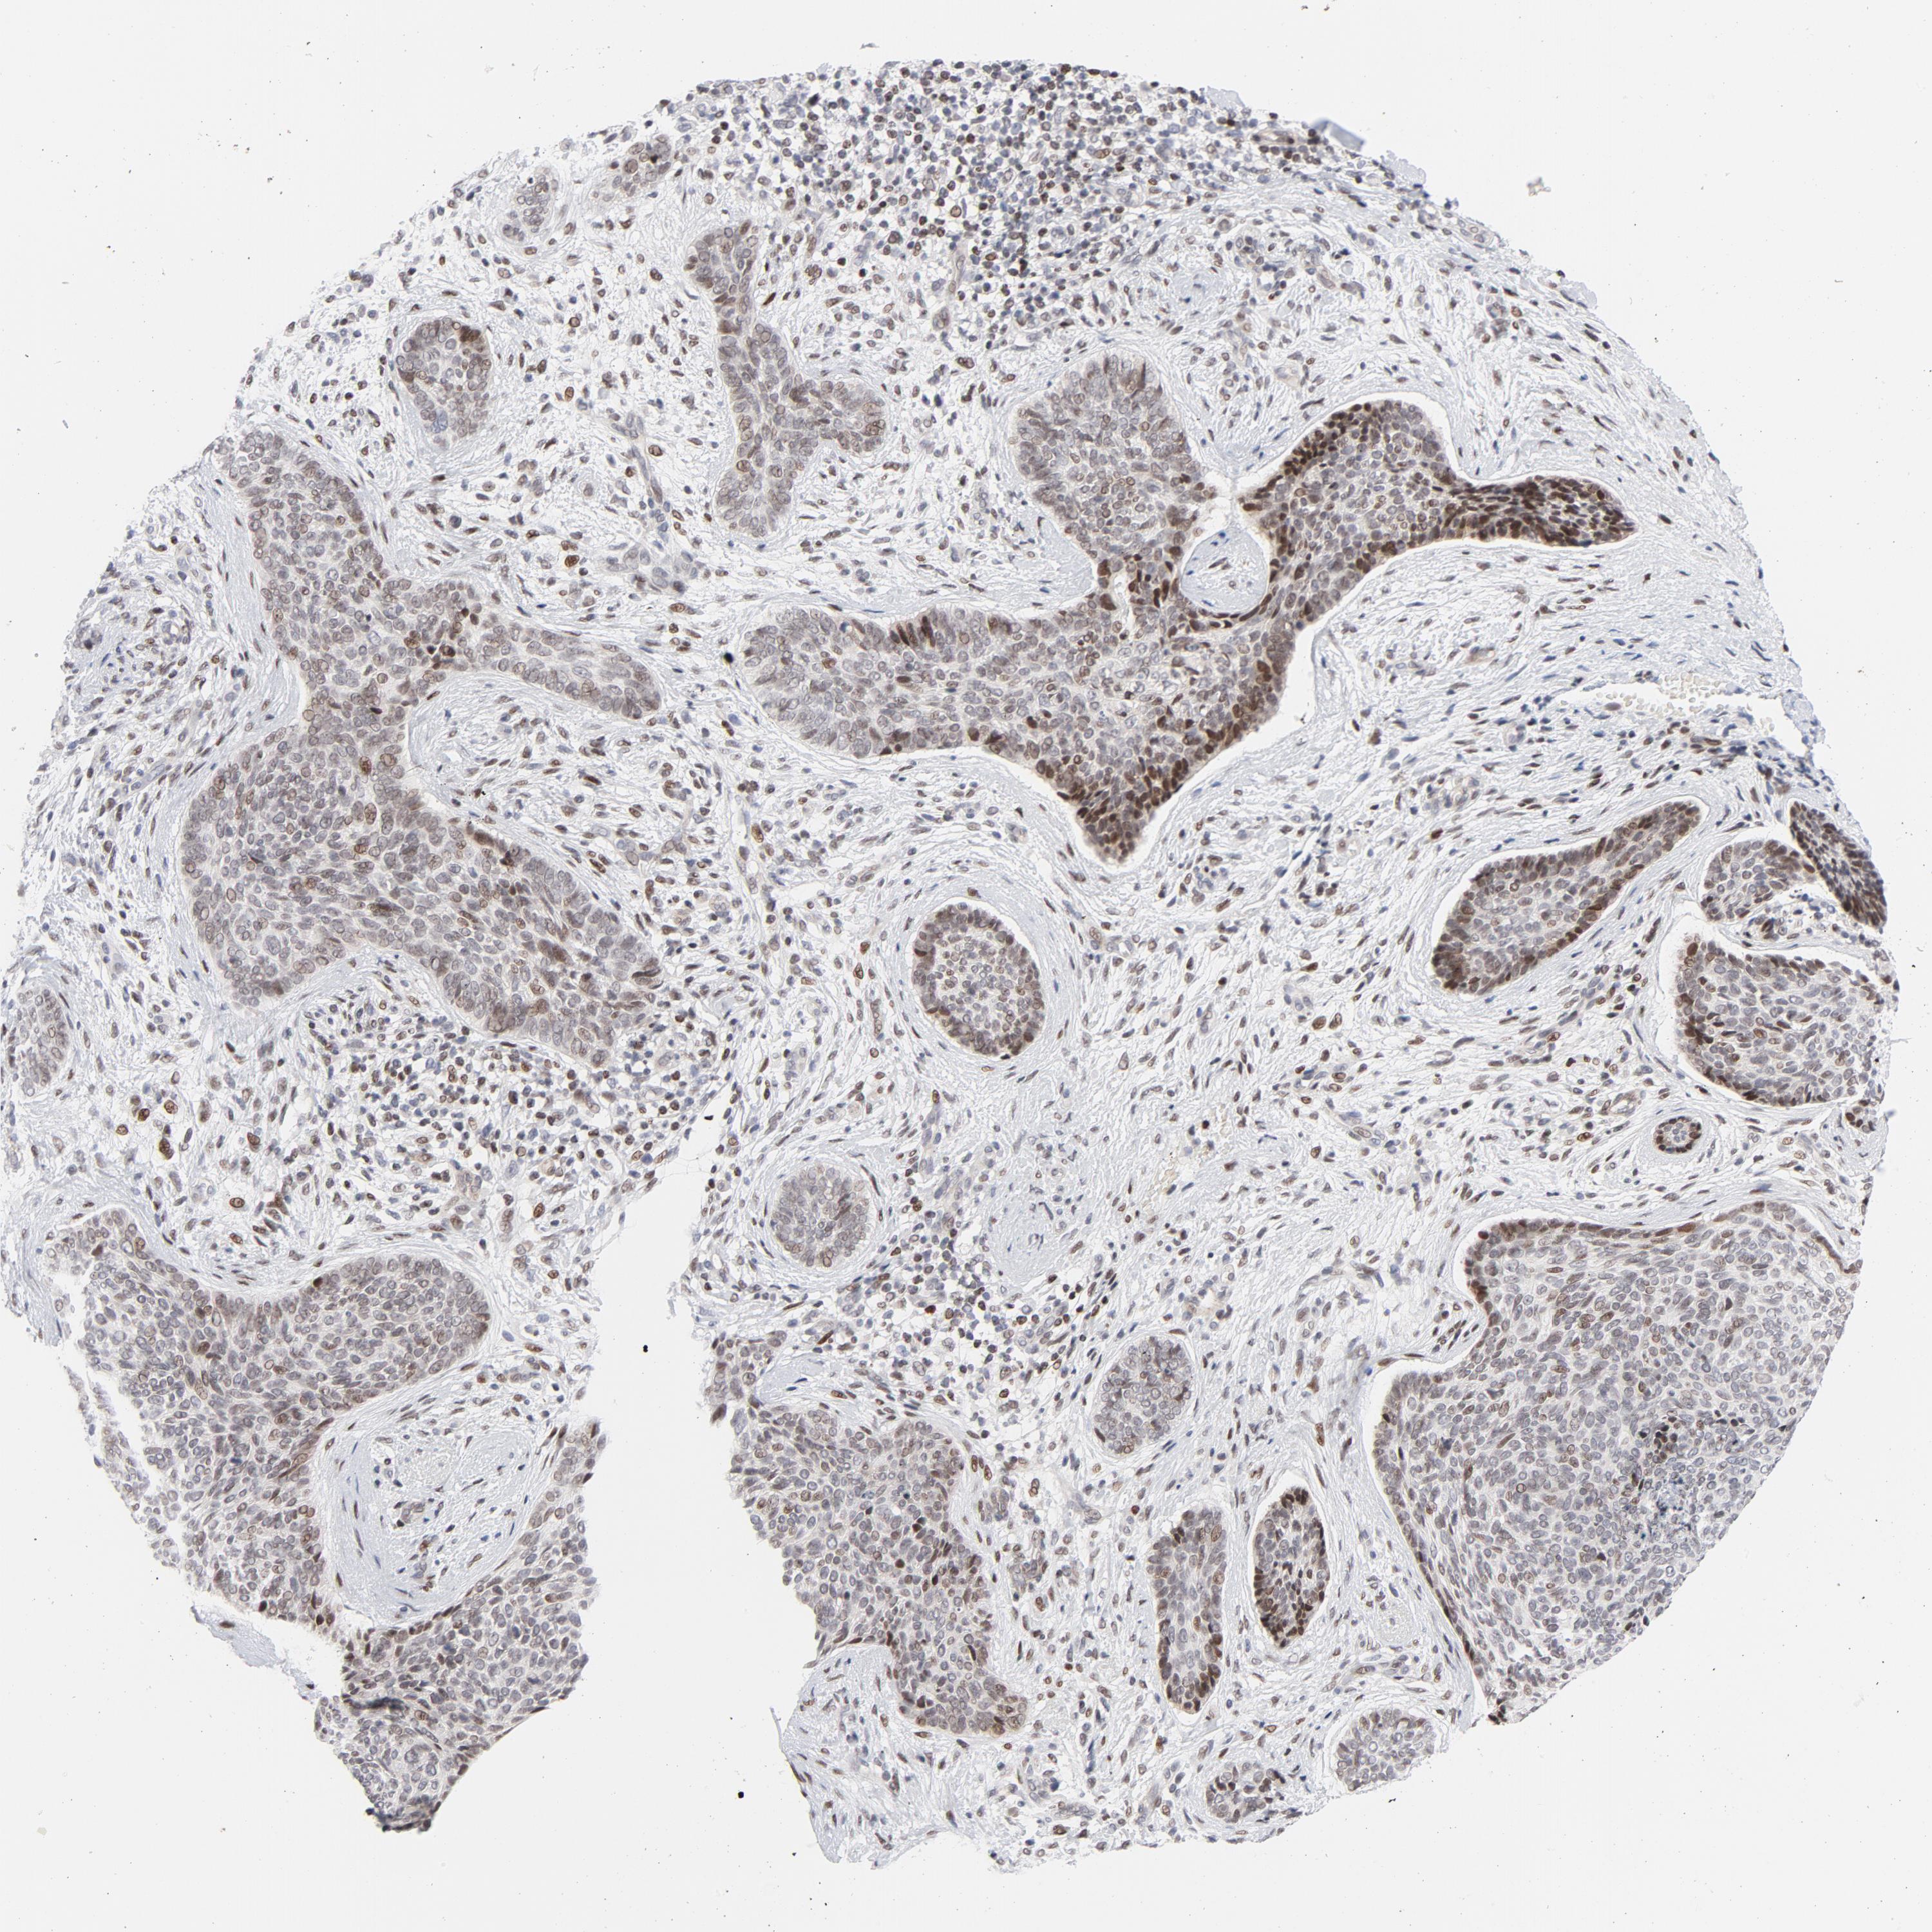

SKIN CANCER - Protein expressioni

A mouse-over function shows sample information and annotation data. Click on an image to view it in a full screen mode. Samples can be filtered based on level of antibody staining by selecting one or several of the following categories: high, medium, low and not detected. The assay and annotation is described here.

Antibody stainingi

Antibody staining in the annotated cell types in the current human tissue is reported as not detected, low, medium, or high, based on conventional immunohistochemistry profiling in selected tissues. This score is based on the combination of the staining intensity and fraction of stained cells.

Each image is clickable and will lead to virtual microscopy that enables deeper exploration of all samples and also displays staining intensity scores, fraction scores and subcellular localization as well as patient and tissue information for each sample.

Antibody CAB004300

Staining

High

Medium

Low

Not detected

Intensity

Strong

Moderate

Weak

Negative

Quantity

>75%

75%-25%

<25%

None

Location

Nuclear

Cytoplasmic/membranous

Cytoplasmic/membranous,nuclear

Basal cell carcinoma

Squamous cell carcinoma, NOS